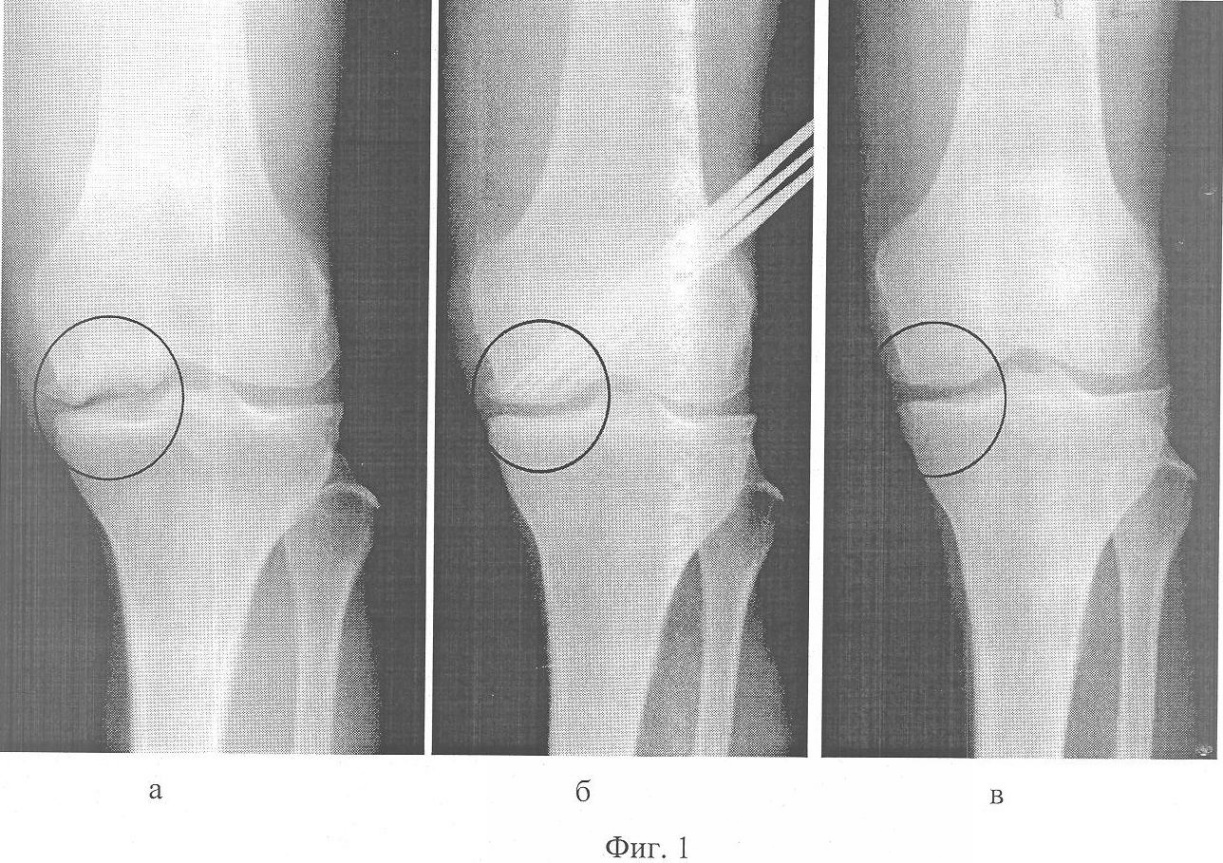

фиг.2 – Компьютерные томограммы левого коленного сустава: а, б) до лечения; в, г) через 6 месяцев после лечения.

При клиническом обследовании: варусное отклонение левой голени при стоянии на 5°, сгибательно-разгибательная контрактура левого коленного сустава 90-165°. При пальпации по внутренней поверхности правого коленного сустава отмечала болезненность. На рентгенограмме левого коленного сустава в прямой проекции – признаки гонартроза, характеризующие II стадию процесса, во внутреннем мыщелке левой бедренной кости костно-хрящевой дефект неоднородной структуры со склеротической границей вокруг очага деструкции и прерывистостью линии хрящевой поверхности мыщелка (Фиг.1а). На компьютерных томограммах патологический очаг локализован в заднем отделе внутреннего мыщелка бедренной кости. Дефект по площади составлял половину контактной поверхности мыщелка (Фиг.2а, б).

При рентгенологическом обследовании через 6 месяцев после операции (Фиг.1в) структура кости в проекции патологического очага перестройки однородная, непрерывность хрящевой поверхности восстановлена, склероз отсутствует. По данным компьютерной томографии коленного сустава – в заднем отделе внутреннего мыщелка бедренной кости отмечается восстановление структуры кости, структурно костный дефект активно восстанавливается (Фиг.2в, г).